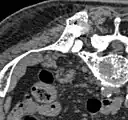

Scanner sagittal reconstruit, représentation dans la fenêtre osseuse. Comme la patiente avait des métastases dans toutes les régions du corps, elle ne pouvait pas lever les bras pour l'examen, ce pourquoi les mains sont présentées.

Scanner sagittale, parties molles. Outre les métastases dans la colonne vertébrale, qui envahissent en partie le canal médullaire vers l'arrière, métastases aussi dans le sternum. Plus des métastases dans le foie.